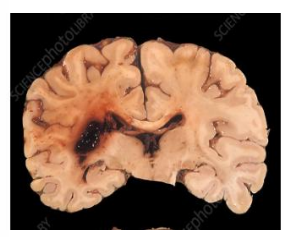

Cerebral infract (early stages)

Cerebral infract